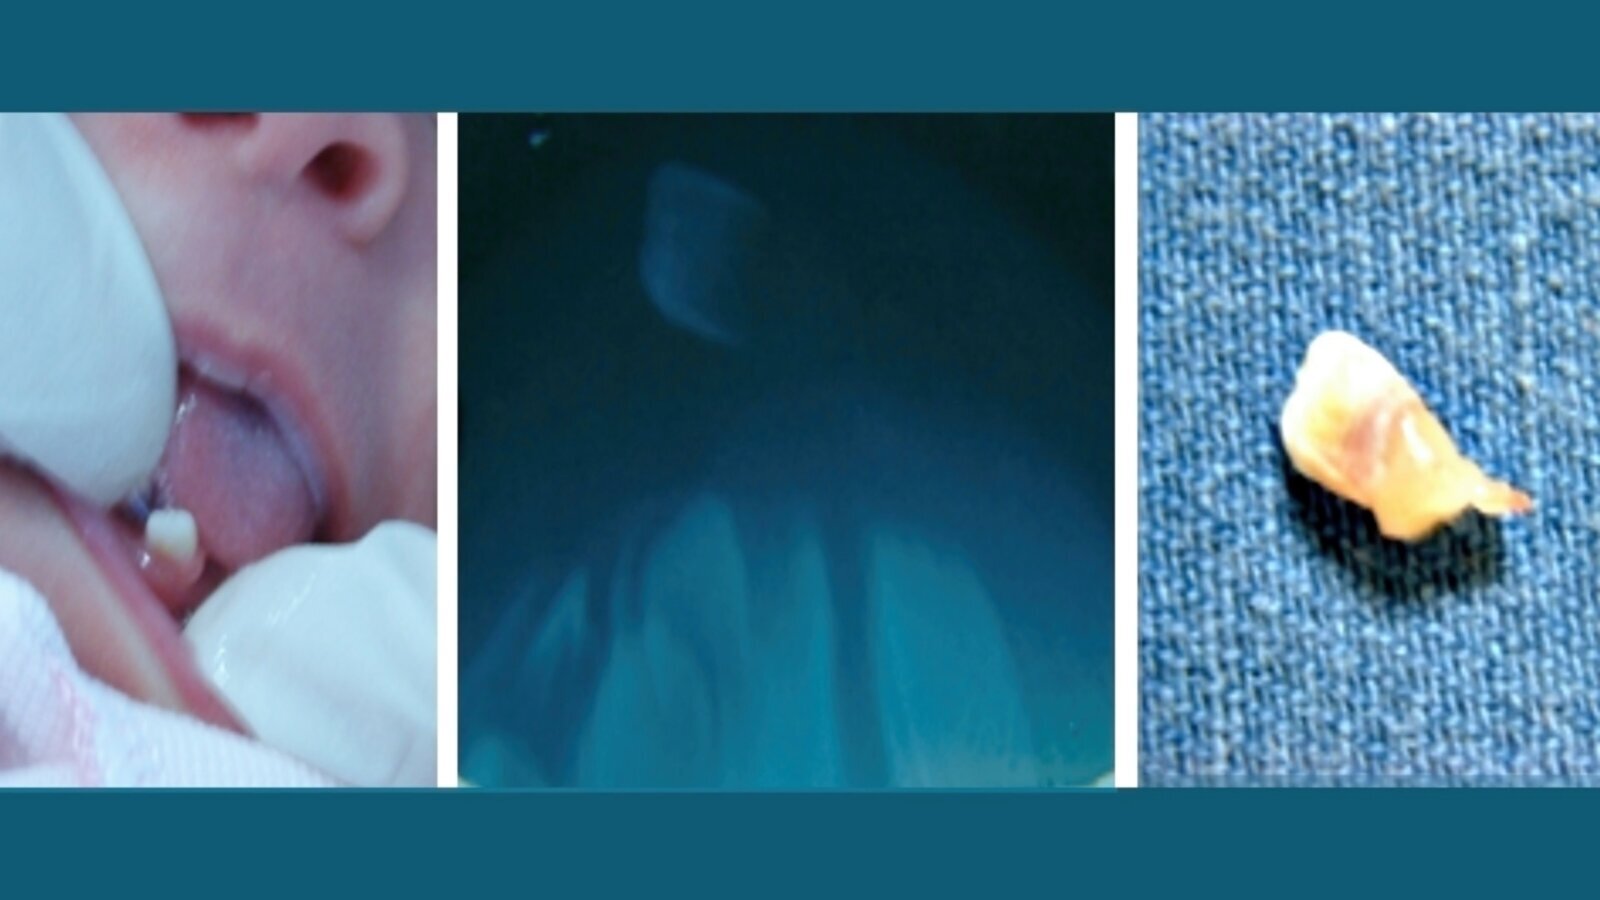

Figura 1. Diente natal. A: Vista clínica. B: Vista radiográfica de diente supernumerario sin implantación. C: Pieza extraída: no hay desarrollo radicular y se observa tejido pulpar abundante.

Se define como diente natal o connatal a aquel que ya ha erupcionado al momento del nacimiento del niño, y como diente neonatal al que hace erupción en las primeras semanas de vida (Figura 1)1.

Al erupcionar sin raíz y/o poco tejido dentario calcificado y/o ausencia de cemento, se mantiene en boca por un anillo fibroso al tejido del maxilar. Por cortes se ha visto que el tejido pulpar es de gran tamaño y muy vascularizado. Esto lleva a pensar que esta pulpa de gran tamaño es una de las causas de su erupción prematura.

Son pequeños, con esmalte irregular, fijados al alveolo por un tejido conectivo fibroso. Erupcionan a) en buena posición y con poca movilidad, o, b) inclinados y movibles. El diagnóstico diferencial se basa en discernir si pertenecen a la serie normal o a dientes supernumerarios1.